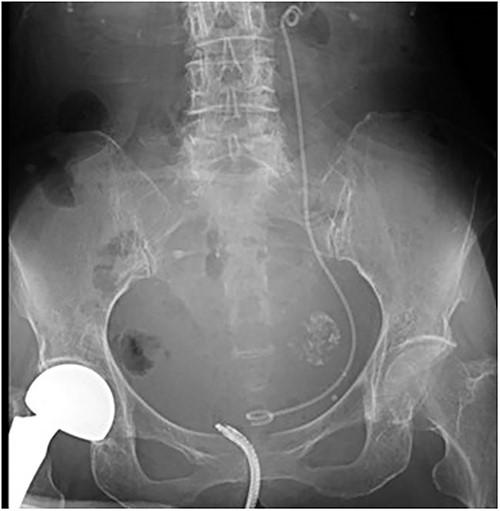

Forty-five days after the stent placement, the patient visited the emergency department complaining of fever and hematuria. CT showed that the left hydronephrosis had reappeared, and the lower end of the stent had migrated into the ureter (Fig. 3a and b). Blood tests revealed a worsening of renal function and a prominently elevated inflammatory response. Due to the diagnosis of relapse of left obstructive acute pyelonephritis caused by the migration of the ureteral stent, an emergency nephrostomy was performed promptly, and antibiotic treatment was started. The patient was discharged after 2 weeks of hospitalization.

Abdominal CT scan; (a) CT demonstrates the position of proximal coil formation in the left renal pelvis; (b) CT demonstrates proximal stent migration into the ureter.